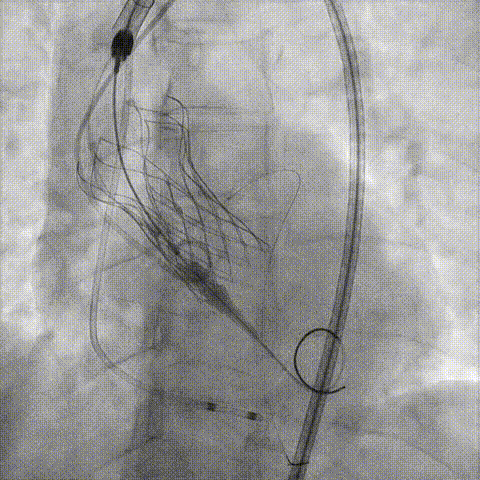

决定左冠烟囱支架保护冠脉

调整支架位置

释放冠脉支架

释放瓣膜

造影评估

支架内后扩张

冠脉造影

根部造影

● TAVR术中,对于有冠脉风险的病人,冠脉保护是保证手术成功安全的重要环节。单用普通指引导管预留导丝是远远不够的,因瓣膜扩张或瓣架释放后,原生瓣膜的移位变形已经使原有冠脉开口情况发生变化,出现开口受压阻断等情況,经普通指引导管无法送入快速及时的置入支架、保护冠脉,故务必在置入辦膜前预先留置Telescope™于冠脉内,Telescope™头端位置务必进入冠脉开口内,保证Telescope™于冠脉内的稳定性,一旦开口受压,迅速经Telescope™送入支架,可选用“烟囱”等技术于冠脉开口释放支架,保证开口血流通畅。Telescope™独有的螺旋线圈技术灵活柔软可以深入冠脉;Smoothpass技术保证了支架置入的快速顺畅;头端柔软安全不损伤冠口,是TAVR术中冠脉保护不可或缺的重要器械。